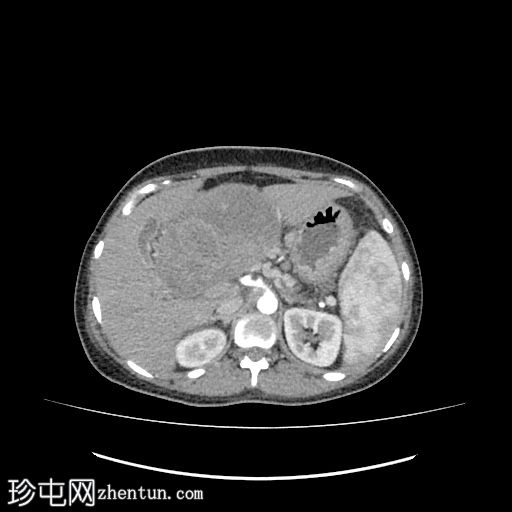

CT

轴位

平扫

肝下区可见一大小约15 x 15.2 x 8.6 cm的较大、边界清晰、呈不均匀强化的实性肿块。

该病灶压迫胃小弯、幽门和胃窦,并对肝脏产生占位效应。门静脉和下腔静脉受压,但脂肪间隙保持完整,未见明确的血管侵犯。

肿块左侧可见正常的胰尾。胰管未见扩张。

肝内胆管和胆总管管径正常。

腹主动脉旁可见亚厘米级淋巴结,最大者短轴直径为 3.5 mm。

中度弥漫性腹水,少量左侧胸腔积液。